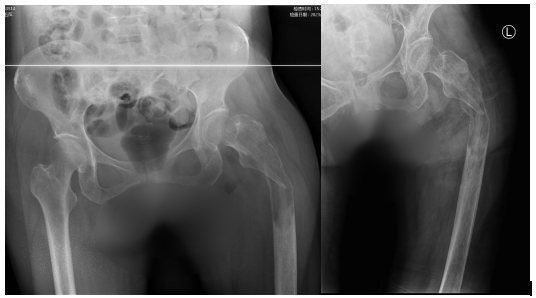

术前影像显示:患者左股骨中上段骨质破坏、病理骨折,骨折移位明显

乐国平教授及其医疗团队了解到梁女士的情况后,一边不断鼓励患者,给予人文关怀,一边积极组织院内MDT会诊,为患者寻求更佳的治疗方案。最终,保肢治疗方案——左股骨上段肿瘤广泛切除、股骨肿瘤假体重建术获得了团队专家及患者一致通过。

经过术前充分的准备以及术中的精细操作,15cm长度的股骨上段肿瘤被完整切除,患者成功装上了髋关节肿瘤假体。术后一周,梁女士在医护人员的帮助下,通过积极的治疗和康复锻炼,已能在助行器的帮助下下地行走。